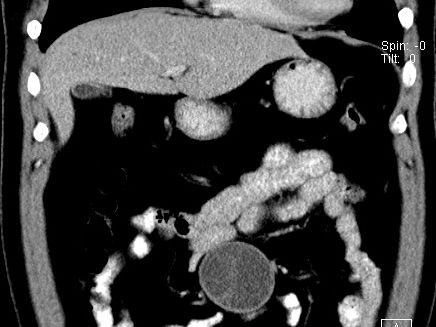

(腹腔)神经鞘瘤

男,48岁,间断性下腹不适1年。

手术探查

:距回盲部28厘米处肠系膜根部可见5*7cm左右包块,质中等硬度,活动度尚可,肝、胆、胰、脾肾未见明显异常。

病理

:(腹腔)

神经鞘瘤

,伴出血、坏死及囊性变,伴淋巴结反应性增生。

免疫组化结果

:sma(-), desmin(-), cd117(-), s-100(+++), nf(-),vimentin(+++).